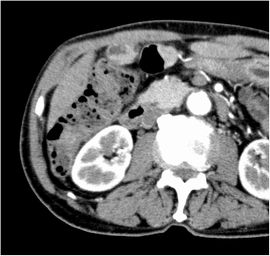

CT検査にて胆嚢底部に限局性に壁肥厚を認め、精査の結果、悪性病変疑いと診断。腹腔鏡下胆嚢摘出術を施行した。病理結果は胆嚢がんであった。

CT画像